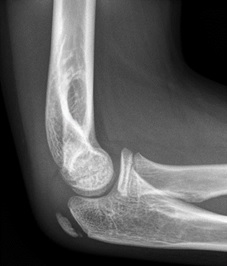

Example X-rays

|

Anterior fat pad seen but NOT elevated, so NOT a joint effusion |

Anterior fat pad elevated off anterior surface of humerus = joint effusion |